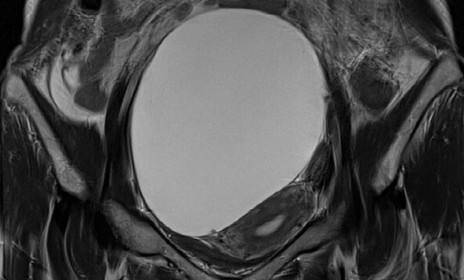

자궁근종 로얄하이푸

거대 근종부터 다발성 근종까지 부작용 최소화 제거

- 정교한 타겟팅 기술로 임신 가능성 보존

- 실시간 초음파 모니터링을 통한 안전 확보

- 재발 방지를 위한 체계적인 사후 관리 케어